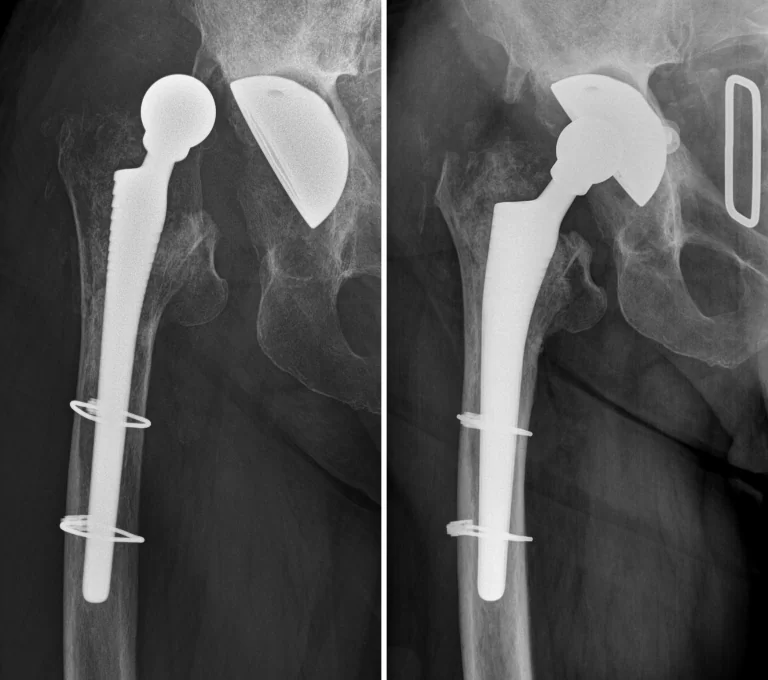

antibiotikum tartalmú ideiglenes csípőprotézis - spacer

A csípőprotézis szárának befogadására gyakran alkalmatlan a combcsont korábbi csípőízülethez közelebb eső felső része, így általánosságban hosszabb, akár reteszelt szárakat szükséges beültetni, csontpótlással, lemezeléssel és/vagy húzóhurok (cerclage) alkalmazásával együtt. Általánosságban elmondható, hogy revíziók során cement nélküli rendszerek alkalmazása van előtérben.